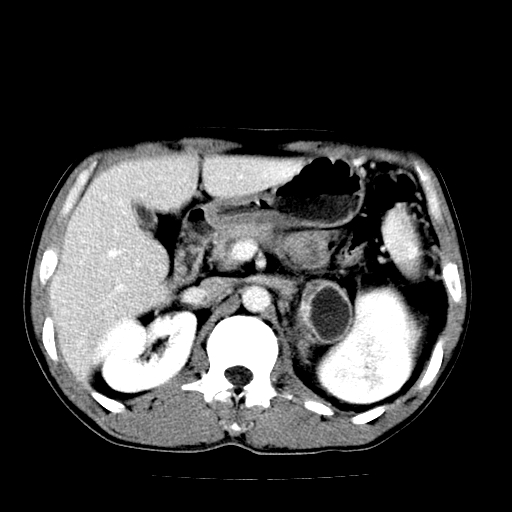

以下是引用天南地北在2007-4-30 13:36:00的发言:[br]支持慢性胰腺炎伴有假性囊肿

以下是引用andymaomao在2007-4-30 14:28:00的发言:[br]支持:1.慢性胰腺炎并假性囊肿形成可能;[br] 2.左肾形态稍增大,旋转不良。